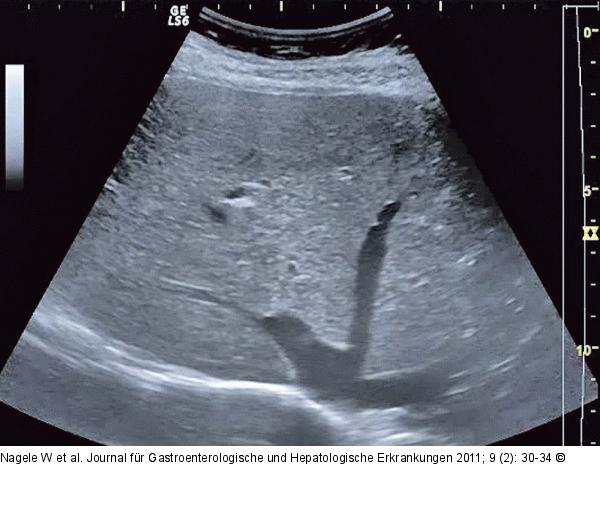

Abbildung 6: Ultraschall-Abschlussbild Ultraschall-Abschlussbild ohne Hinweis auf fokale Leberveränderungen. |

Ultraschall-Abschlussbild ohne Hinweis auf fokale Leberveränderungen. |